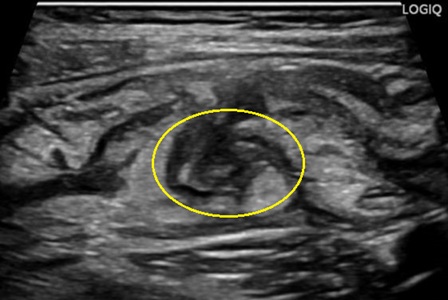

大腸憩室炎の超音波(エコー)画像

- 画像検査:CTやエコー検査

・憩室の存在、周囲脂肪織濃度上昇(炎症)、膿瘍や穿孔の有無を確認 - 大腸内視鏡:急性期は穿孔リスクのため原則行わない